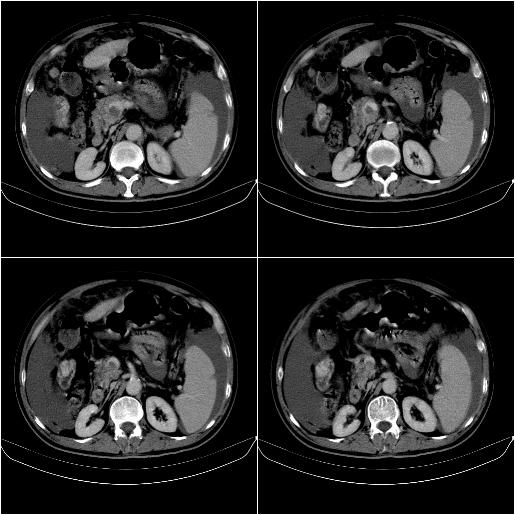

m,67y,肝癌9月,介入术后3月。现腹胀、纳差、腹泻。

1)肝癌介入治疗术后碘油沉积不良。2)门静脉瘤栓形成,腹膜广泛性转移。3)肝硬化,脾大,腹水。4)慢性胆囊炎。